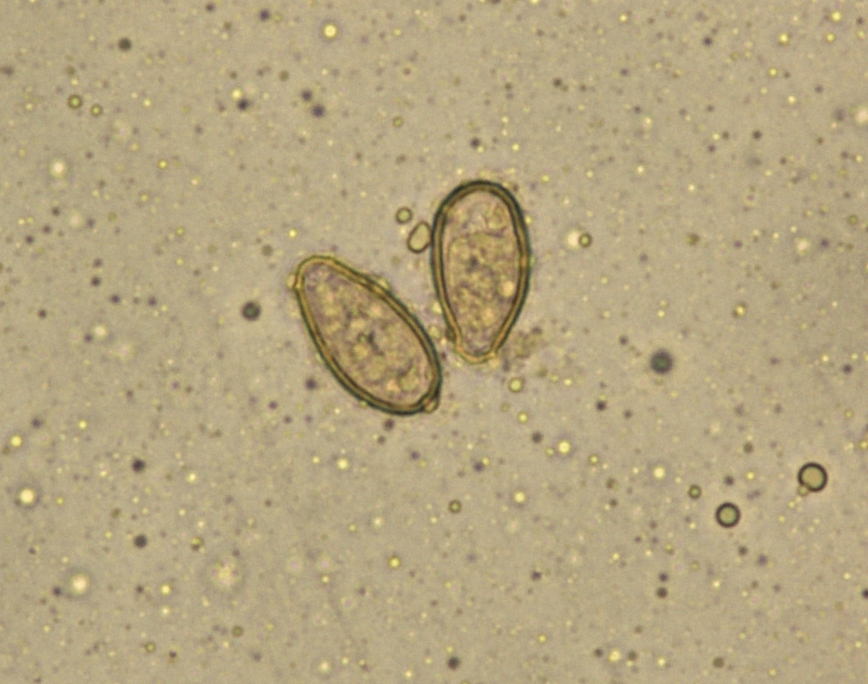

Что такое яйца гельминтов в сточных водах - фото презентация